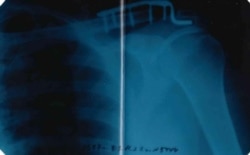

Металлическая пластина в плече, рентген

35-летнего жителя Красноярска Якова в сентябре мобилизовали, несмотря на металлическую пластину на месте травмированного сочленения лопатки и ключицы. В учебной части из-за усиленной нагрузки у него отнялась рука. Возвращать его домой командование отказывается – вместо необходимой операции его угрожают "отправить на спецоперацию".

– В 2013 году Яков попал в ДТП, разорвалось сочленение ключицы и лопатки, ему поставили на этом месте металлическую пластину с винтами. Почти 10 лет он жил с этой пластиной вполне нормально, так как плечо берег, не перегружал, – говорит мать мобилизованного Татьяна Николаевна (имя изменено по просьбе героини). – В конце сентября сыну пришла повестка, но никакой медкомиссии не было. Яков сказал в военкоматах (он в двух был – в Октябрьском и Железнодорожном районах) о пластине в плече, но его даже слушать не стали! Напротив, стали нагружать, как всех здоровых. Плечо стало болеть, а к началу ноября правая рука просто отнялась.

В начале ноября Якова направили в гражданский травмпункт в Херсонской области, где врач подтвердил, что требуется операция, и выдал справку о необходимости удалить металлоконструкцию.